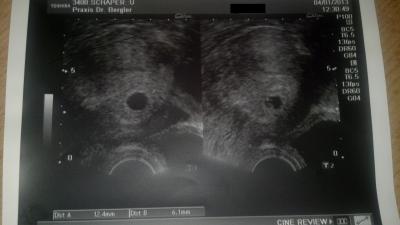

Heute war ich das erste Mal beim FA. Es ist alles supi, der Krümel ist jetzt 6,1mm groß. Wurde zwar auf den 2.9. ausgerechnet, da ich aber immer zum Ende hin mit HELLP zu tun habe, wird es bestimmt noch ein Augustkind. Meine momentan Jüngste kam wegen HELLP auch 3,5 Wochen vor Termin im Mai 2011. LG Kerstin

Bild zu Auch ich bin jetzt so richtig dabei! War heute beim FA.... - Forum für August - Mamis